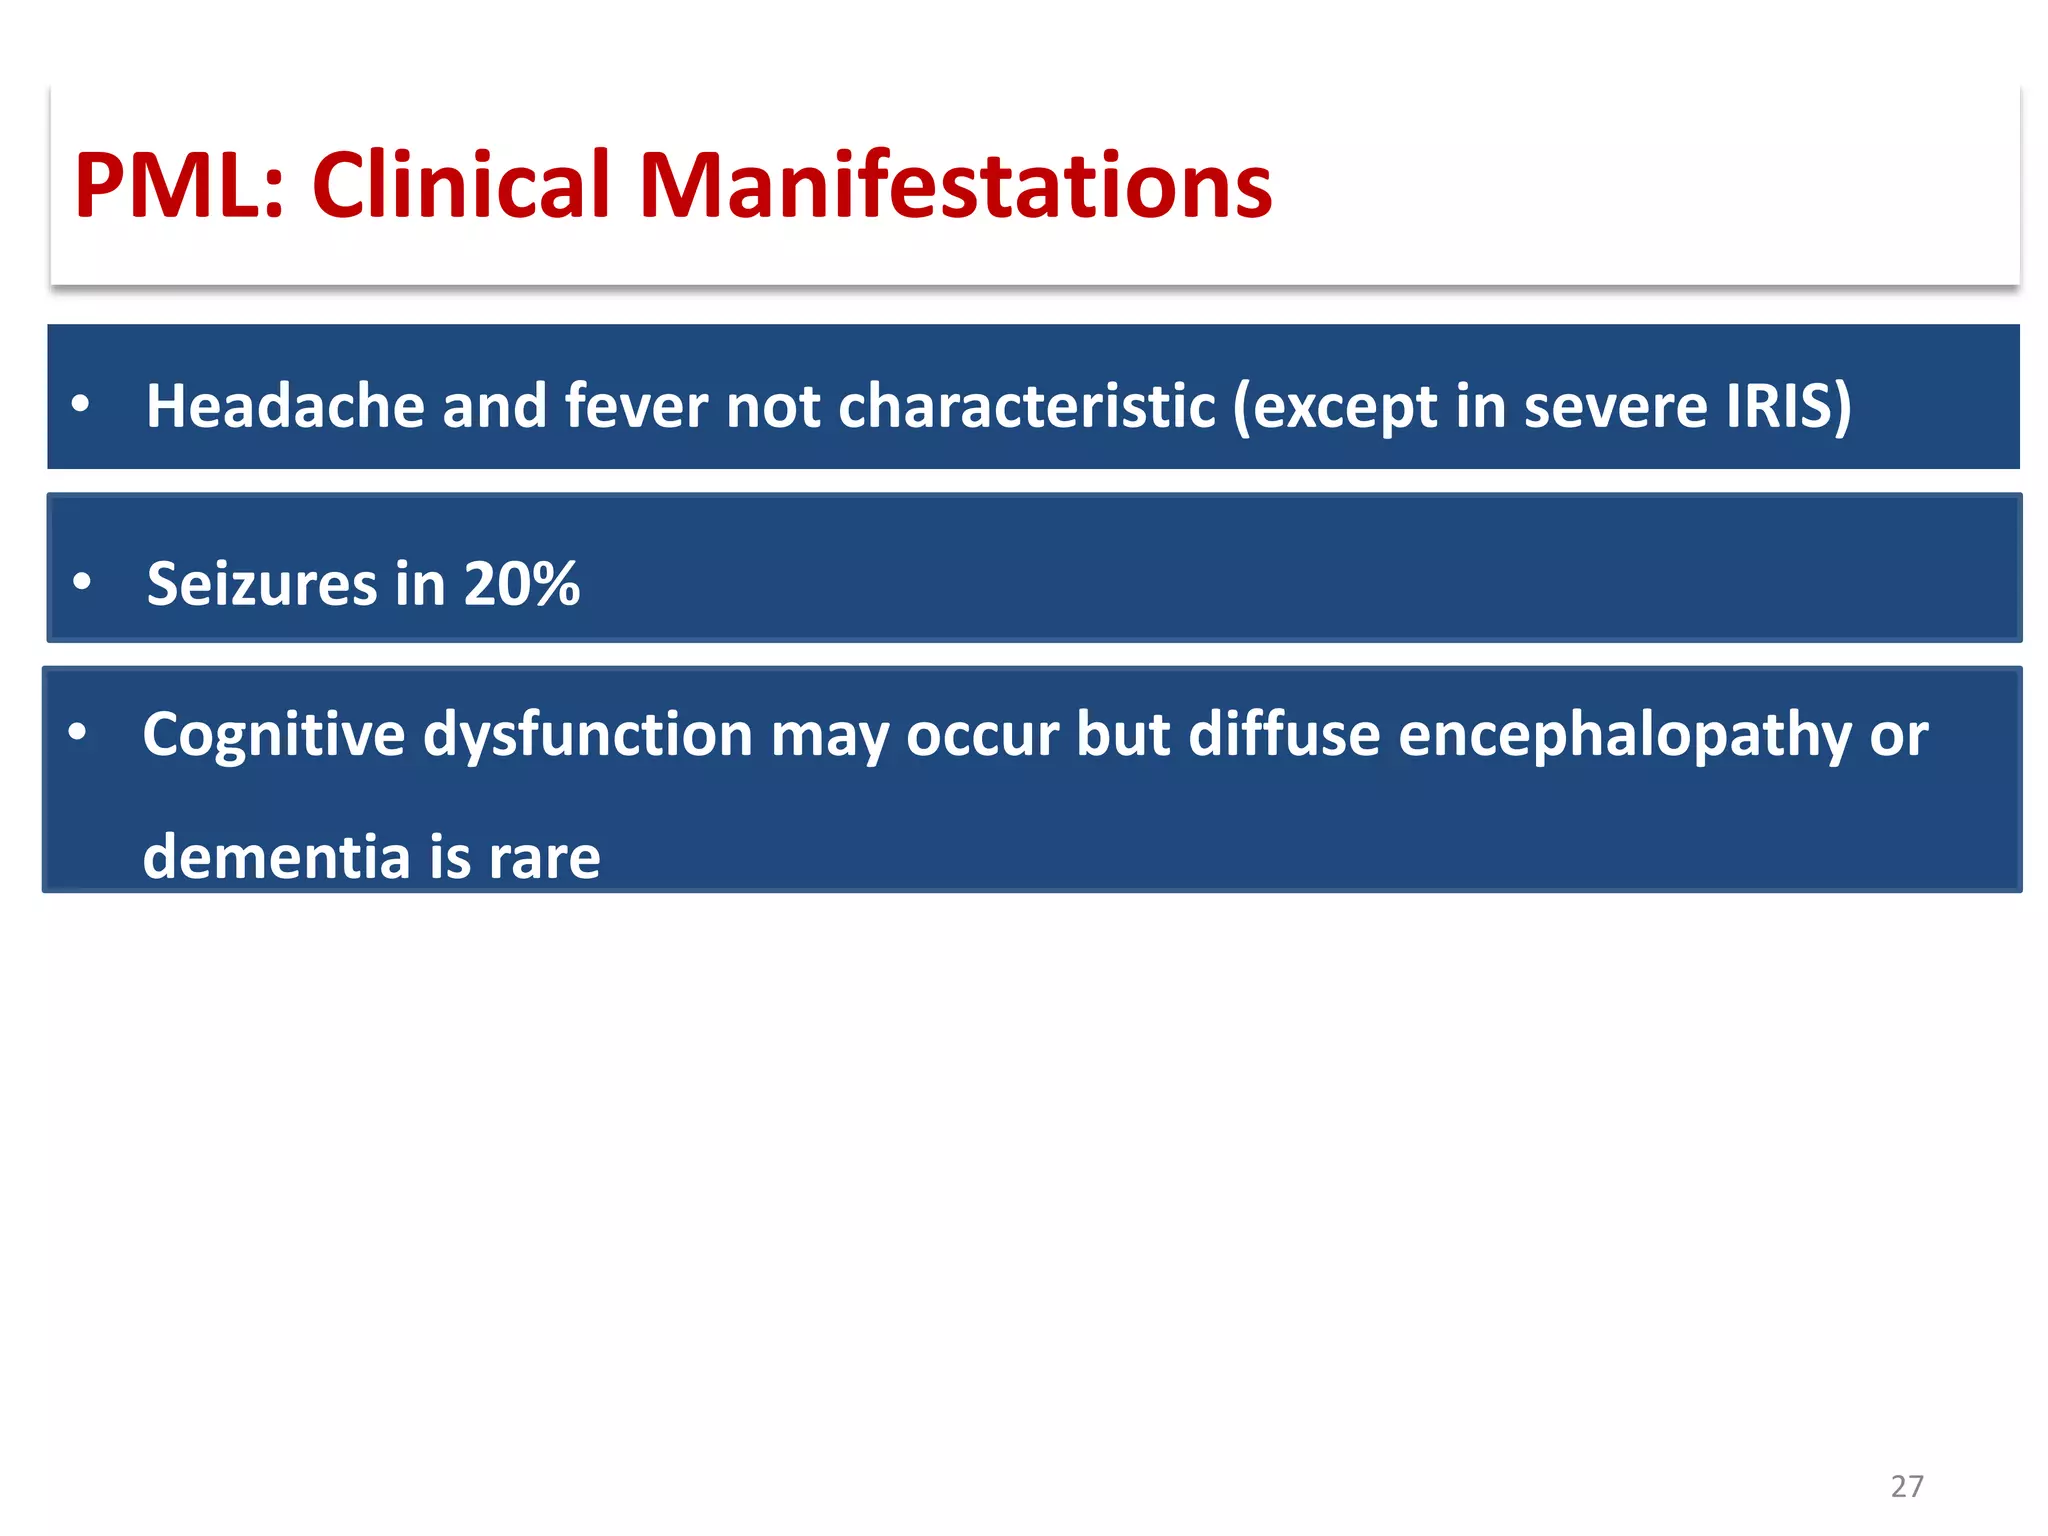

This document discusses progressive multifocal leukoencephalopathy (PML), an opportunistic infection caused by the John Cunningham virus (JCV) that leads to demyelination in the central nervous system. It highlights the epidemiology, clinical manifestations, diagnostic methods, and risk factors associated with PML, particularly in immunocompromised patients and those undergoing immunomodulatory therapies. It also presents data on the incidence of PML in patients treated with natalizumab and other therapies, addressing the relationships between these treatments and the development of PML.